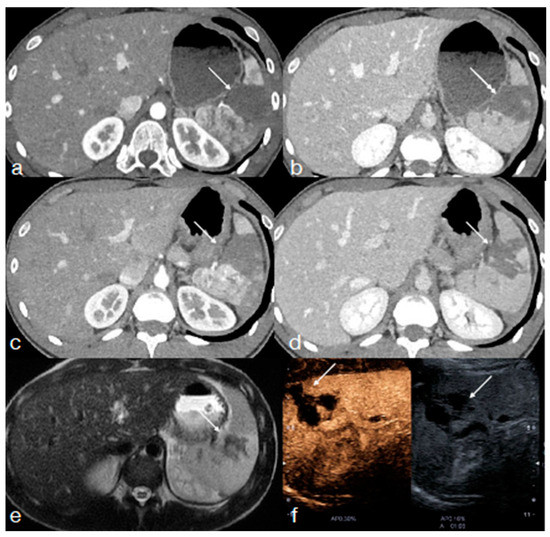

- Miele, V.; Piccolo, C.L.; Sessa, B.; Trinci, M.; Galluzzo, M. Comparison between MRI and CEUS in the follow-up of patients with blunt abdominal trauma managed conservatively. Radiol. Med. 2015, 121, 27–37. [Google Scholar] [CrossRef] [PubMed]